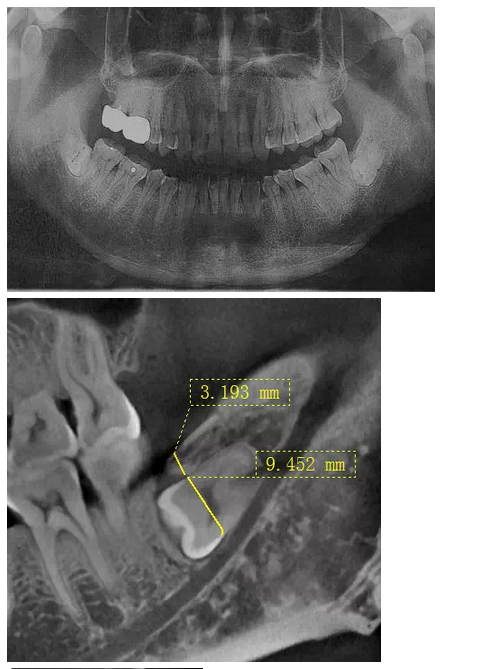

曾有這樣一位痛苦的中年患者,因雙側(cè)胸悶不適困擾二十余年,多處求醫(yī)無果,一次偶然體檢的機(jī)會(huì),拍得口腔曲面體層片(全景片,圖一),顯示下頜雙側(cè)各有一顆水平埋伏阻生智齒,醫(yī)生建議擇期拔除。但患者更關(guān)心此二顆智齒是否是引起自己不適癥狀的原因,均被告知不敢肯定,無法從西醫(yī)角度解釋有何關(guān)聯(lián)。但痛苦驅(qū)使著患者自己去查閱了大量中醫(yī)資料,查得此下頜角處為一穴位,患者遂認(rèn)為可能是這二顆牙齒點(diǎn)中了此穴,導(dǎo)致自己胸悶不適,說服自己之后,來我院就診要求拔除。

沒有CT,在全景片上評(píng)估右下智齒與下牙槽神經(jīng)管距離很近,告知各樣風(fēng)險(xiǎn),患者表示理解并簽字。常規(guī)手術(shù)切口,翻瓣,露得一部分牙冠,去骨后,多次小心翼翼檢查車針深度,使冠根分離,去除牙冠,進(jìn)入取根階段,多次輕力試挺,均無動(dòng)靜,只知牙根與下牙槽神經(jīng)管很近,卻不知具體的三維關(guān)系,所以只好小心翼翼地找間隙,此舉進(jìn)展龜速,如履薄冰,筋疲力盡,猶如兩驅(qū)小轎車行駛在泥濘的小道上,想給力卻打滑。后來還是團(tuán)隊(duì)的力量,輪番上陣,最終全部拔除,拔除后才得知原來是兩個(gè)牙根向內(nèi)直角彎曲,牢牢卡住了中間的牙槽中膈。患者第二天雖然術(shù)后反應(yīng)較大,但是非常開心地告訴我們右側(cè)胸悶有明顯好轉(zhuǎn),而且右側(cè)嘴唇?jīng)]有麻木,所以要求傷口恢復(fù)好之后馬上將左側(cè)的智齒拔除。這給我們帶來了安慰的同時(shí),也給了我們更大的挑戰(zhàn)。

在拔牙一月后,鳥槍換大炮,診所引進(jìn)了三維CT,左側(cè)智齒在拍了CT后,前后頰舌上下關(guān)系就一目了然,此牙更難拔除,因?yàn)橥耆穹▓D二),其上面覆蓋有3mm厚的牙槽骨,其下緣與下牙槽神經(jīng)管緊緊相連,較危險(xiǎn);牙冠前緣與第二磨牙遠(yuǎn)中根也緊緊相連,后緣牙根向上翹;整個(gè)牙齒偏頰側(cè),頰側(cè)皮質(zhì)骨板較厚(圖三),舌側(cè)骨板也較厚,測好牙冠頸部上下距離約為9.5mm。

我們掌握了全方位的信息后,藉著CT向患者講解該牙齒的情況,患者充分理解拔牙的風(fēng)險(xiǎn)和醫(yī)生所需要的經(jīng)驗(yàn)和勇氣。因著有CT,術(shù)前的準(zhǔn)備更加充分:手術(shù)切口的設(shè)計(jì)和種植機(jī)去骨的部位選擇均在第二磨牙的遠(yuǎn)中頰側(cè)(圖四);車針長度的定位在9mm,防止磨到神經(jīng)管;掌握了牙根根尖部分是彎向下(圖五),就可以評(píng)估常規(guī)的挺子是很難進(jìn)去的,特別設(shè)計(jì)了四把不同角度的挺子。整個(gè)拔牙過程非常順利,行云流水,均在我們的掌握之中,猶如四驅(qū)的牧馬,人雖行駛在惡劣的沙漠地,仍是馳騁疆場,酣暢淋漓。